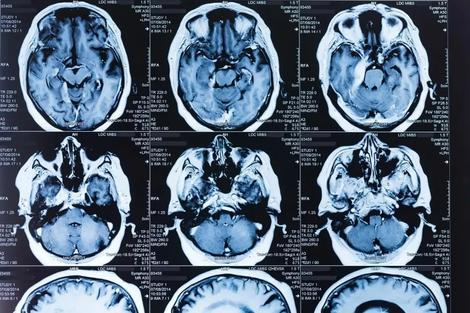

اکثر مطالعات قبلی که نشانگرهای پروتئین پیری مغز را در خون بررسی کرده بودند، شرکتکنندگانی کمتر از هزار نفر داشتند؛ اما وی شی لیو، محقق از دانشگاه فودان چین و همکارانش برای درک بهتر نشانگرهای پروتئینی خون دادههای اسکن مغزی MRI نزدیک به ۱۱هزار بزرگسال از پروژهی بیوبانک بریتانیا را که در آن زمان بین ۵۰ تا ۸۰ سال داشتند، تجزیهوتحلیل کردند.

بهگزارش نیوساینتیست، لیو و تیمش با استفاده از دادههای ۷۰ درصد از شرکتکنندگان، یک مدل هوش مصنوعی را آموزش دادند که بتواند سن شرکتکنندگان را براساس ویژگیهای تصاویر مغزی، از جمله اندازهی نواحی مختلف مغز و نحوهی اتصال بخشهای مختلف به یکدیگر، پیشبینی کند. زمانی که این مدل روی ۳۰ درصد باقیماندهی شرکتکنندگان اعمال شد، پیشبینیها فقط به طور میانگین ۲٫۷ سال با سن واقعی افراد اختلاف داشت.

در مرحلهی بعد، محققان از مدل هوش مصنوعی برای پیشبینی سن گروه جداگانهای متشکل از ۴٬۷۰۰ نفر که به طور میانگین ۶۳ سال سن داشتند، استفاده کردند که از مغز آنها نیز برای بیوبانک بریتانیا تصویربرداری شده بود. تیم تحقیقاتی تفاوت بین سن واقعی این شرکتکنندگان و سنهای پیشبینیشده توسط هوش مصنوعی را محاسبه کردند که شکاف سنی مغز نامیده میشود. لیو میگوید: «هرچه سن پیشبینیشده توسط هوش مصنوعی نسبت به سن واقعی آنها بیشتر باشد، مغز آنها سریعتر پیر میشود.»